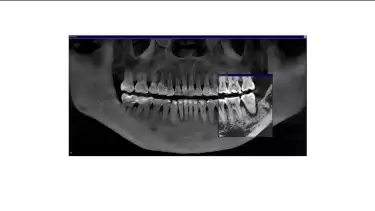

Sebaliknya, hasil rontgen pada gigi kiri menunjukkan kerusakan yang lebih signifikan. Tulang hampir tidak lagi melekat pada gigi, menyebabkan giginya lebih goyang dan sulit dipertahankan.

“Potensi pemulihan gigi sebelah kiri jauh lebih rendah, dan kemungkinan keberhasilannya lebih kecil. Namun, kami tetap berupaya mempertahankan gigi semampu mungkin,” tambah drg. Devya.